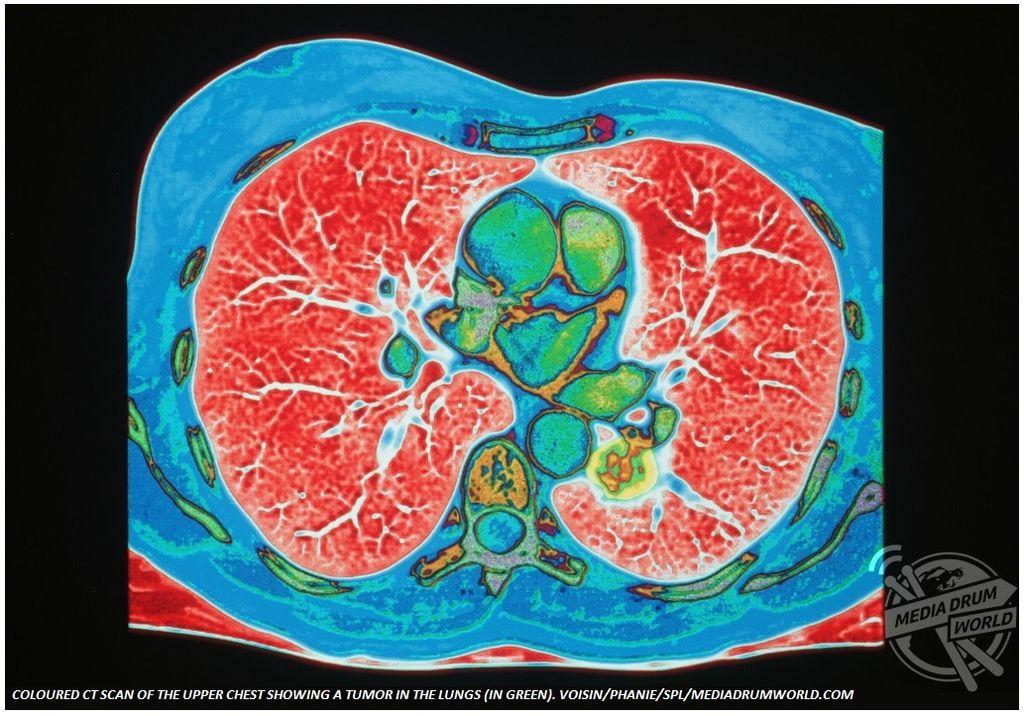

Μερικές από τις σοβαρότερες και πιο επίπονες ασθένειες που δυστυχώς αντιμετωπίζουν πολλοί άνθρωποι, αποτυπώνονται μέσα από φωτογραφίες έγχρωμες. Ασθένειες όπως ο καρκίνος και η αρθρίτιδα γίνονται φωτογραφίες και παίρνουν μορφή.

Από μια ακτινογραφία των δαχτύλων ασθενούς με αρθρίτιδα μέχρι έναν υπέρηχο ενός διογκωμένου προστάτη, οι φωτογραφίες παρουσιάζουν ασθένειες που πλήττουν χιλιάδες ανθρώπους ανά τον κόσμο, προκαλώντας έντονο πόνο και σημαντικούς περιορισμούς στην καθημερινότητα.